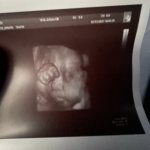

Я сходила сегодня, мне что-то кажется не то с губами) или это пройдёт?

Узист сказала что всё в норме, отекает типа от окоплодных вод)

Я ходила на 30 неделе. Вообщем все совпало. Черты лица прям такие же как в живую.Просто на снимке лицо отёкшее. Нос картошкой, губы тоже одна больше другой.А родилась с курносым носиком и с нормальными губами. У меня вообще когда в первые минуты показали на экране то лицо у неё кривое было сильно. Очень испугалась. А потом нормализовалось все и лежала любовалась ею